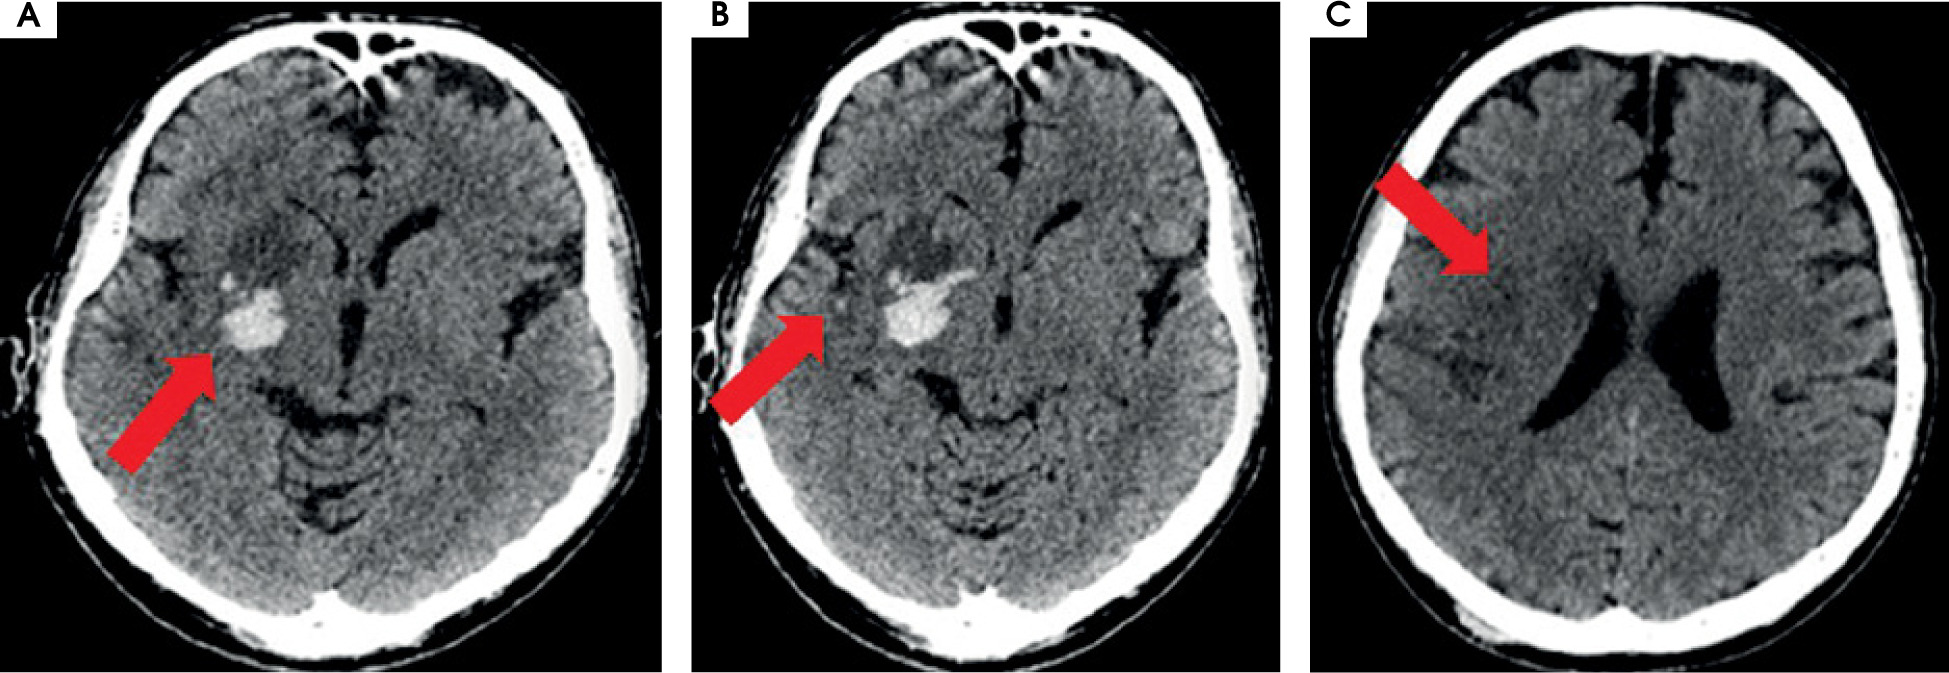

After MT the blood flow in the artery was returned with TICI 3 (Figure II). The day after the MT, control CT showed haemorrhagic foci (Figure III). The patient returned to the ICCU three days later. His neurological status was the same as before the MT of RMCA. In repeated CTs of the brain, haemorrhagic foci were still present (Figure IVA). In the following days of hospitalization, the resolution of haemorrhagic and evolution of ischemic cerebral lesions were observed (Figure IVB).